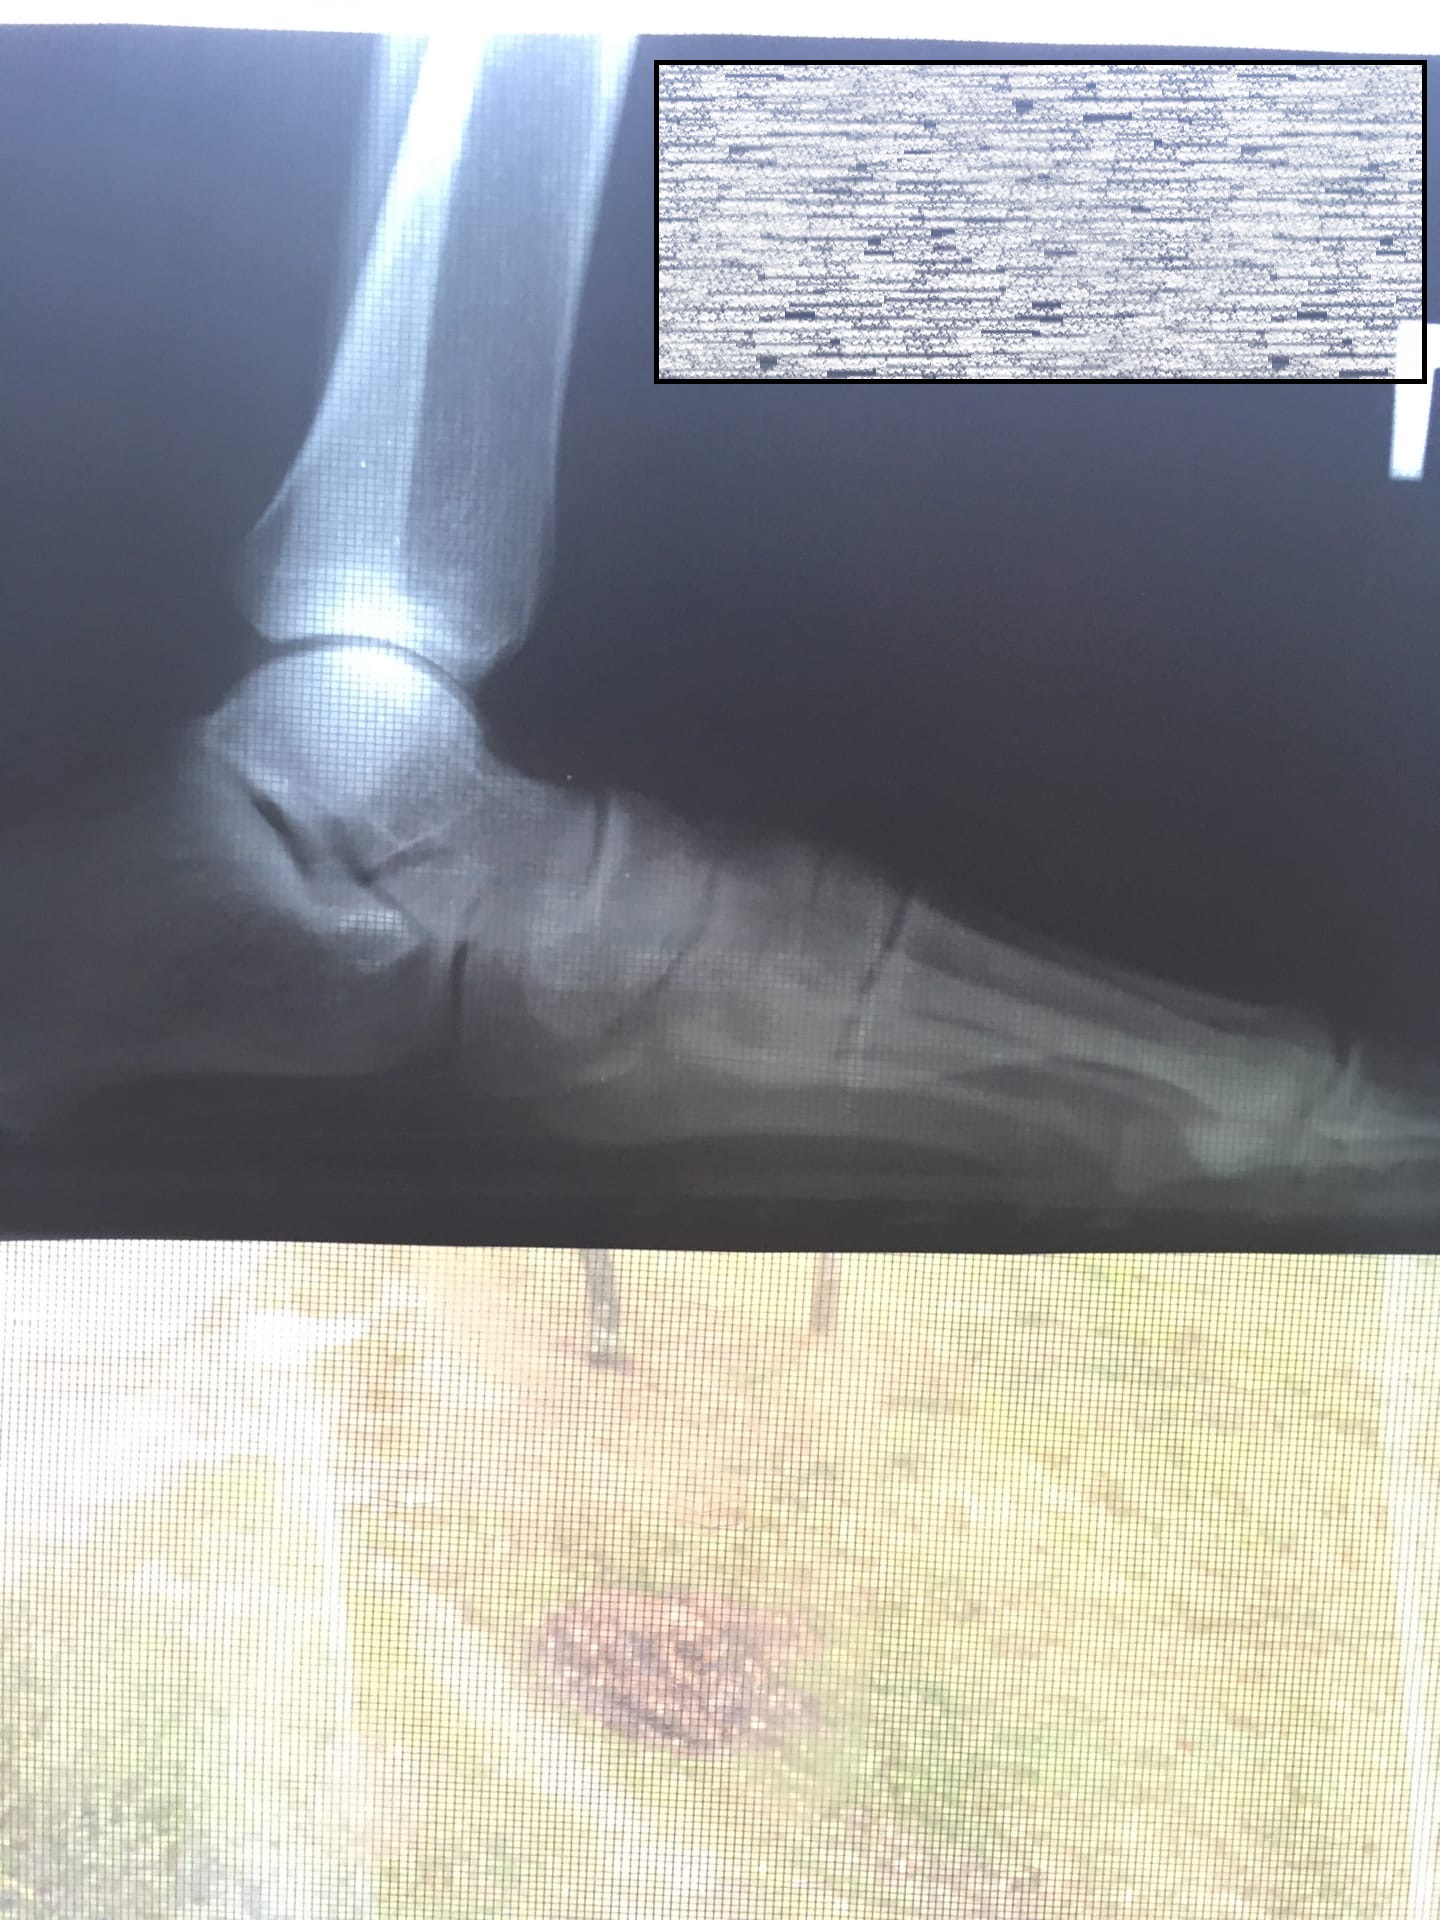

Тут написали, что у меня плоскостопие 3 степени, но правильно ли расчерчили? Просто хочу в армию, но говорят у меня ноги кривые и плоскостопие, но мне кажется, что его нету и верхний угол треугольника слишком низко поставили, где он вообще должен быть? мне кажется где соединяются те две кости, то есть тут 13мм, а там было бы 21 и я годен

Дело в том, что я пока делал рентген не от военкомата, и хотел посмотреть какая у меня степень, может от военкомата расчерчат правильно? и правильно ли расчерчили вообще, фото ренгена во вложениях